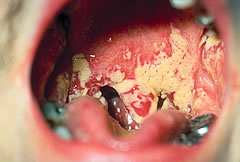

Candida albicans es un hongo que se halla habitualmente en el tracto gastrointestinal y genitorinario sin producir enfermedad. Sin embargo, en niveles elevados puede producir aftas e infecciones fúngicas. La infección de C. albicans se complica o incluso puede ser letal en personas inmunodeprimidas o aquellas que utilizan antibióticos de amplio espectro, siendo un problema potencialmente grave en ambientes hospitalarios o centros asistenciales.

Esencial para la proliferación de la infección es el biofilm, un grupo de células de Candida albicans dispuestas en forma de lámina. Éstas células producen componentes como proteinas y azúcares que forman una matriz similar al cemento. Ésta matriz protege las células del biofilm, haciéndolas resistentes a los medicamentos y propiciando la infección.